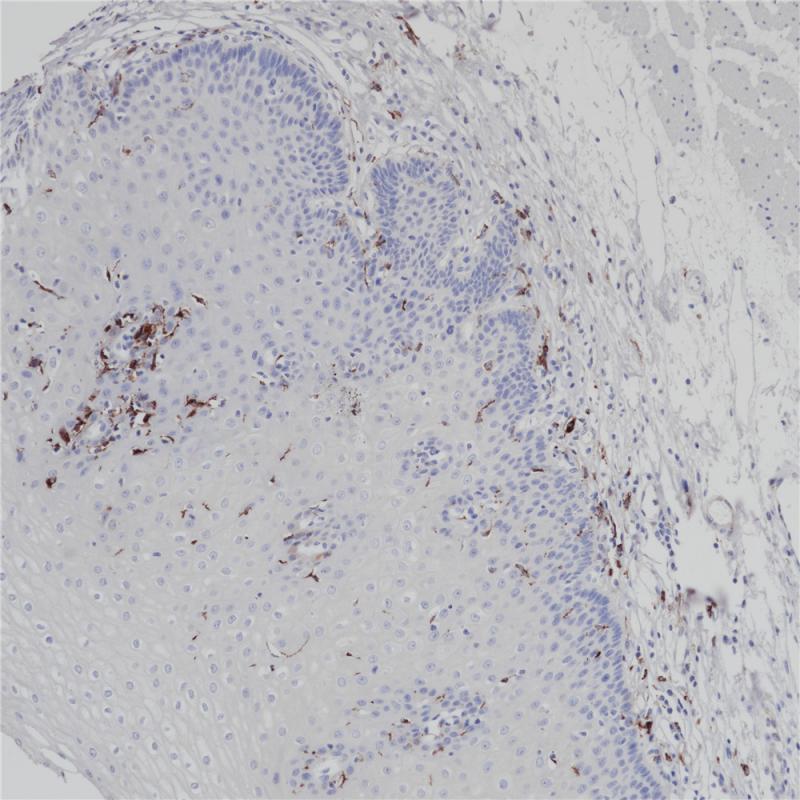

Cytokeratin 8&18 Cocktail

细胞角蛋白8&18表达于所有单层上皮,尤其是各种腺上皮。 该抗体能够识别50及43kDa的低分子量角蛋白,对应的Moll分类为CK8与CK18,主要用于鉴别诊断鳞癌与腺癌

阳性对照

结肠

亚细胞定位

细胞质